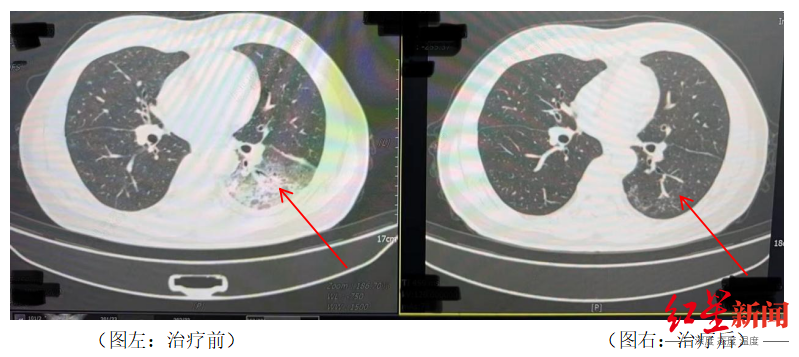

李先生肺部治疗前与治疗后的对比

据报道,李先生开了3天空调后,出现了肌肉酸痛、头痛、发热和咳嗽等症状。起初,他以为是吹空调吹感冒了,于是自行服用感冒药,但病情并未好转,反而愈发严重。家人见状,立即将他送往成都市第五人民医院感染性疾病科。胸部CT显示李先生的左肺已出现大面积白色影像,几乎占据一半肺部。经过肺泡灌洗NGS检测,最终确认“罪魁祸首”是嗜肺军团菌。